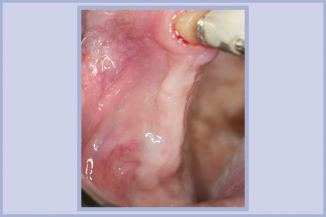

Dopo 6 mesi dall’intervento i tessuti molli appaiono in buona salute (fig. 21).

- Fig. 21